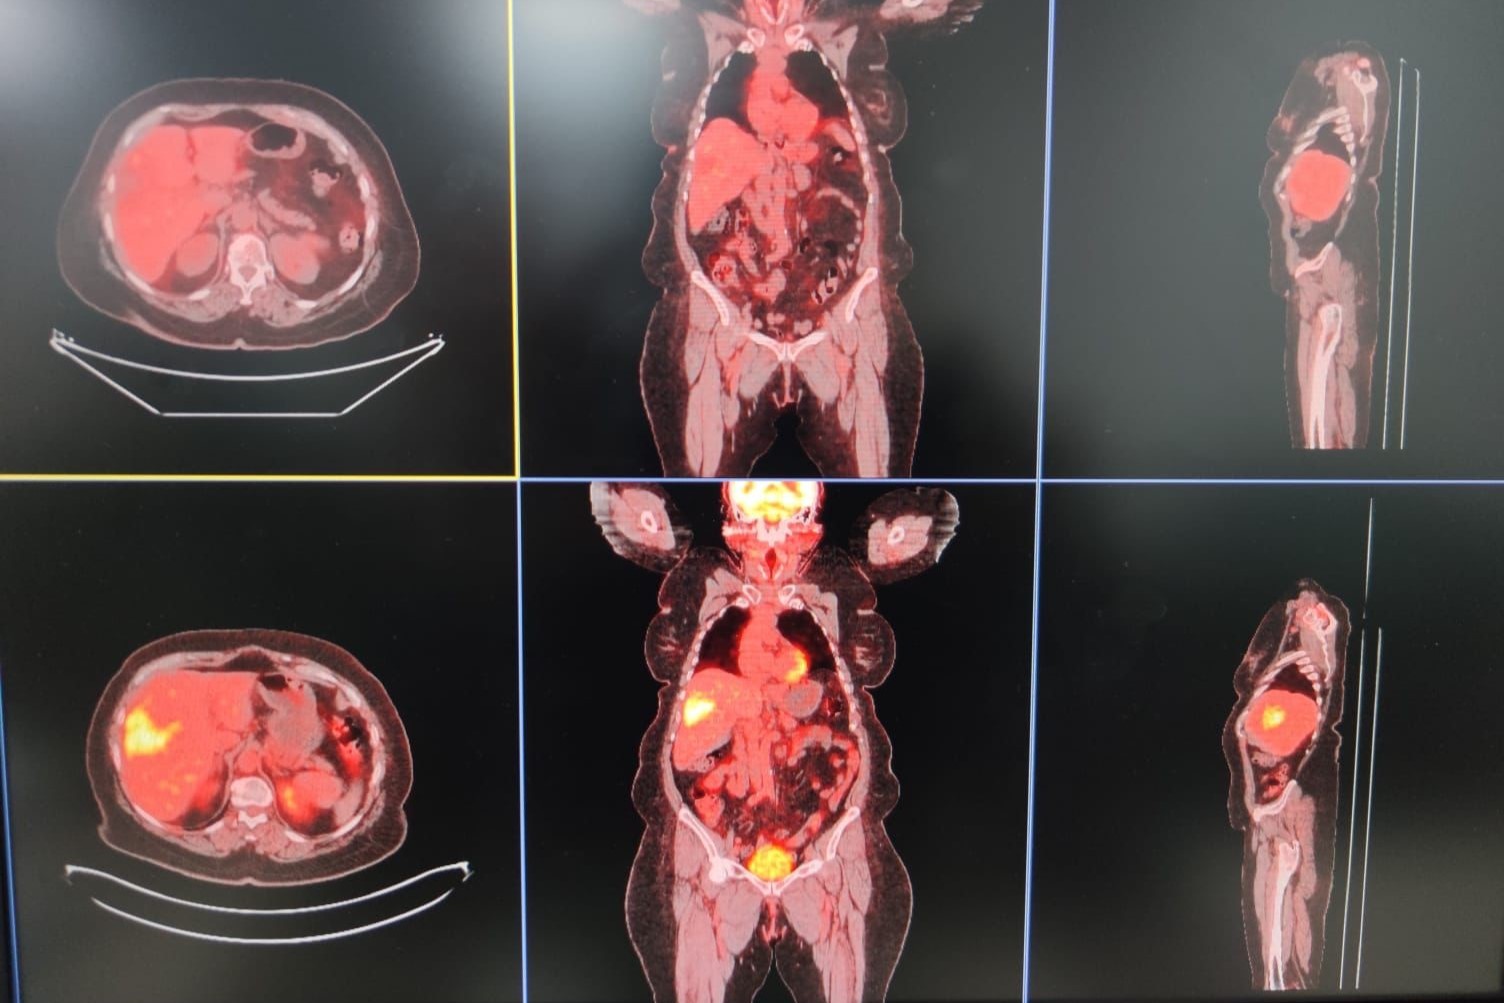

Bir kısmının da tedavisini yapıyoruz. TARE işlemi; belli organlardaki tümör hücrelerine hedef kitleyi besleyen damarın içine girip buna lokal olarak radyoembolizan dediğimiz maddenin enjekte edilmesiyle gerçekleşen bir işlemdir.

Bu işleme yaygın olarak karaciğerin kendi tümörleri ile başka organlardaki tümörün yayılımlarını tedavi ediyoruz” dedi.

Kitlenin besleyici damarı bulunup buraya bir prova olarak asıl vereceğimiz ilaca benzer bir ilaçla enjeksiyon yapılıyor. Daha sora nükleer tıp biriminde ilacın o kitleyi ne kadar tuttuğu hesaplanıp uygun dozlarda asıl ilaç dozu hesaplanır.

Bir sonraki seansta aynı şekilde daha önce belirlediğimiz damarın içine girip radyoembolizan dediğimiz küçük parçacıklara radyoaktif maddeler yüklüyoruz.

Biz bu parçacıkları küçük küçük doku içerisine gönderip hem belli bir süre tıkama hem de lokal olarak vücudun diğer taraflarına etki etmeden sadece kitleye etki edip onu öldürme yöntemini kullanarak tümörü tedavi ediyoruz” diye konuştu.